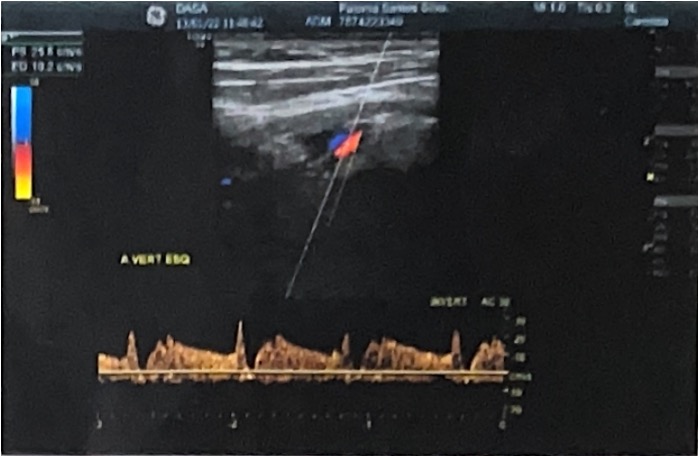

Arco da Aorta à Direita e Roubo de Fluxo Arterial: Relato de Caso

Luciana Yukie Nakagawa, Ana Caroline de Mélo Viana, Maria de Fatima de Lira Silva, Adriene Gonçalves Mota, Renan de Lima Rocha, Marcelo Calil Burihan, Renata Nunes da Silva

bjcr113